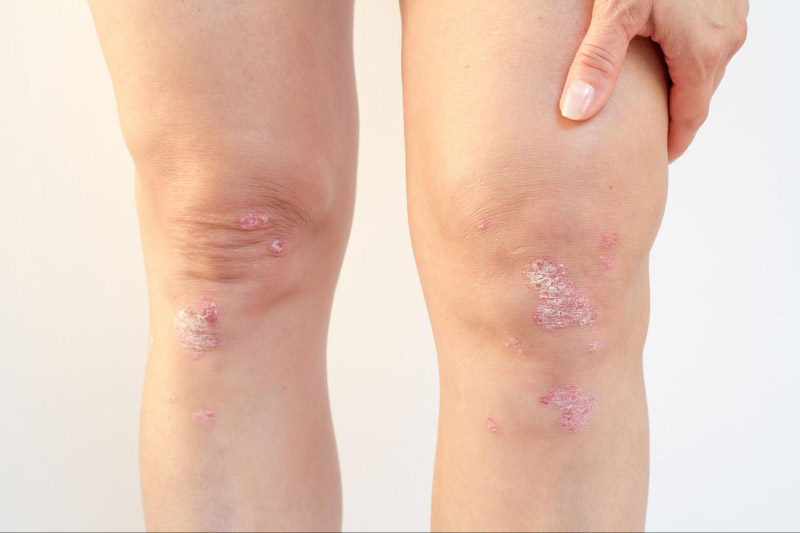

Viêm khớp vảy nến (Psoriatic arthritis) cũng là một bệnh lý tự miễn, diễn ra ở các bệnh nhân mắc bệnh vảy nến gây tổn thương ở da với các biểu hiện như phát ban đỏ, vảy da, móng tay dày và rỗ. Một trong những triệu chứng đặc trưng của bệnh lý này là gây cứng và sưng ngón tay, ngón chân, đồng thời ảnh hưởng đến các khớp, cột sống, hệ tiêu hóa,… theo mức độ từ nhẹ đến nặng.